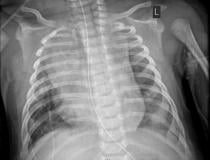

This photo gallery shows the variety of radiological presentations of COVID-19 (SARS-CoV-2) in medical imaging, including computed tomography (CT), radiograph X-rays, ultrasound, echocardiograms and magnetic resonance imaging (MRI). The radiology images show examples of typical COVID pneumonia in the lungs and the numerous complications the virus causes in the body in multiple organs, including the brain, kidneys, heart, abdomen and vascular system.

Ultrasound, especially hand-held ultrasound imaging devices, have become a primary imaging modality for novel coronavirus because of the ease to bag the device and sterilize it after use. CT and mobile X-ray systems are also used as front-line imaging systems for COVID-positive or suspected COVID patients.